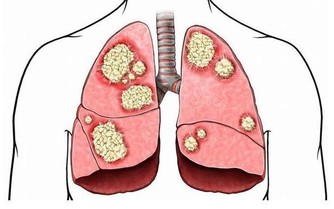

李大爺這傷口已經是典型的糖尿病足了,大家都知道一旦得了糖尿病足,潰瘍進展是很快的,而且很難癒合,所以李大爺就因為這傷口在我們科住了半個多月,還沒有痊癒,可以說是“一失足成千古恨”。

可以肯定的是,合理、科學、正規的辨證中藥泡腳可以起到溫經通絡的作用,對於預防糖尿病下肢血管病變及糖尿病足具有很好的效果。但是部分患者自行購買一些刺激性比較強的中藥或其他成分不明的藥物泡腳,或者到不正規的按摩保健“診所”進行“祖傳秘方”的“傳統治療”,這種刺激性過強的藥物容易導致足部皮膚受損,出現膚色變暗、紅腫、乾裂、破潰等,最終發展成為糖尿病足。